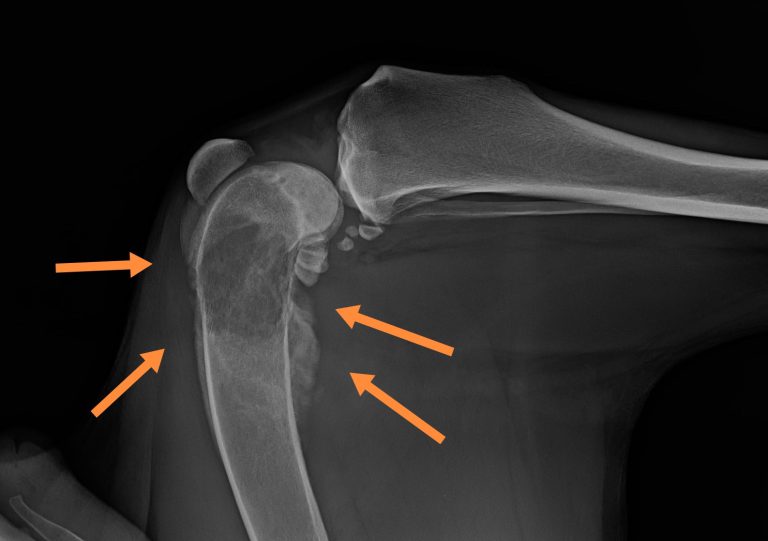

Krónikus, gyógyszerrezisztens sántaságnál, tapintható csontkemény duzzanat esetén a régió röntgenvizsgálata javasolt első körben. Az osteosarcoma (vagy más csontdaganat) esetén a csontok állománya felhőszerűen megritkul, a röntgeneken kissé molyrágtának tűnik, ezzel egyidejűleg a külső felszínen csontfelrakódások is kialakulnak, a csonthártya pedig sokszor elemelkedik, ami nagyon jellemző az osteosarcomára.

Erősen meggyengült csontszerkezet esetén annak patológiás törése, beroppanása is látható lehet. A röntgenfelvételeken látható csontoldódással járó elváltozások fertőző- vagy rosszindulatú folyamatra utalnak, ezért minden esetben további diagnosztikai vizsgálatok javasolhatók.